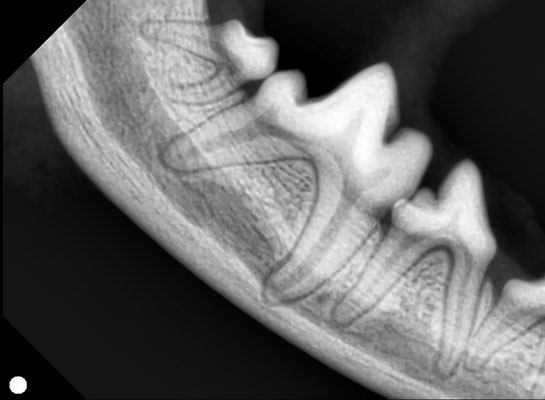

上のレントゲン写真は、犬の奥歯を撮影したものです。

2枚目(正常):歯の根まで骨がしっかり残っており、健康な状態です。

歯科レントゲンを撮ることで、外からは見えない歯の根や骨の状態まで確認できるのが大きな特徴です。

歯の根や周囲の骨の状態が分かる